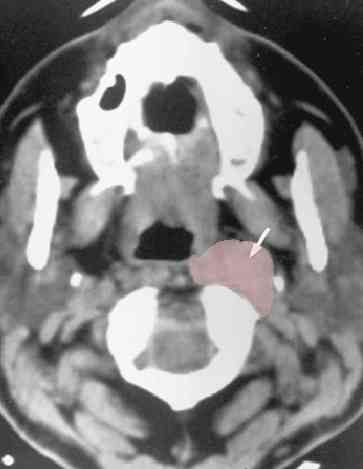

CT normal anatomyCTCTpic#1 and pic#2, CT advanced nasopharynx cancer